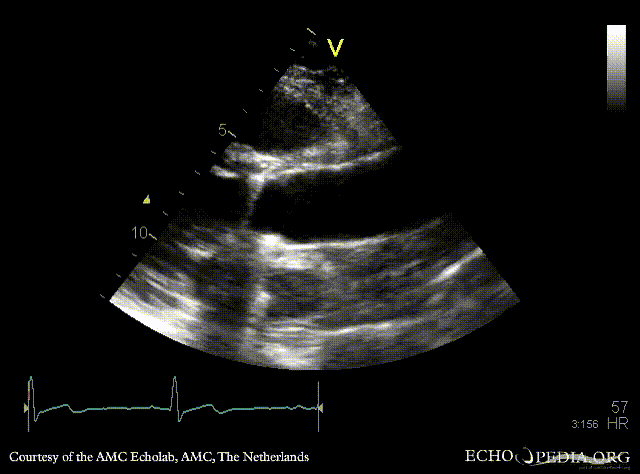

Bentall and aortic valve prosthesis

Courtesy of: AMC Echolab, AMC, The Netherlands

PSAX: aortic valve prosthesis and Bentall in situ PSAX with Color Doppler